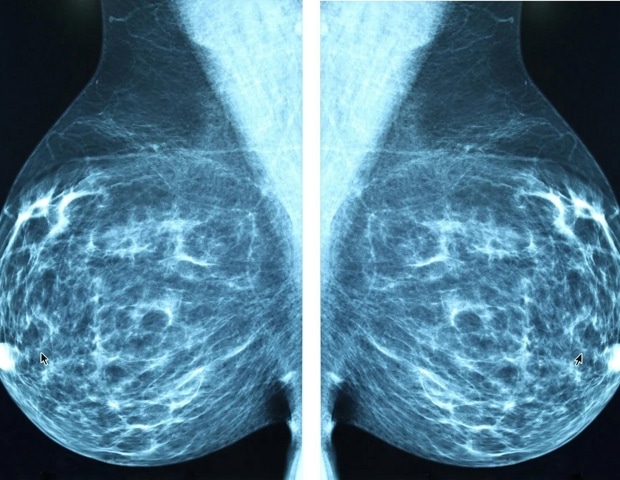

Исследование выявило рост заболеваемости раком молочной железы у молодых женщин

По данным исследования, представленного сегодня на ежегодном собрании Радиологического общества Северной Америки (RSNA), исследование данных семи амбулаторных учреждений в регионе Нью-Йорка показало, что 20–24% всех случаев рака молочной железы, диагностированных за 11-летний период, были обнаружены у женщин в возрасте от 18 до 49 лет.

Новые национальные тенденции подчеркивают рост заболеваемости раком молочной железы у молодых женщин, что побуждает к переоценке возрастных порогов скрининга и стратегии стратификации риска.